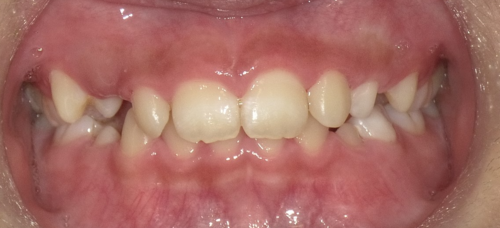

タイプⅢは受け口や交叉咬合に使います。大人の場合は顎の成長が止まっているので、反対咬合・受け口の場合は歯の軸を変えて治す場合と遺伝的に下顎そのものが大きい場合は外科手術で下顎の骨を切って治す場合があります。小児の場合は、まだ下顎の成長が始まっていないので、できるだけ上顎を積極的に成長させなければなりません。受け口・反対咬合だと、下の前歯が上の前歯の前にあるので、上の顎が前方に成長するのを妨げてしまうので、受け口だったら出来るだけ早くに改善する必要があります。下の写真のように短期で改善することが出来ます。

↓

最初から8カ月で受け口は改善していますし、さらに歯と歯の間に隙間が生じているので歯列が拡大しているのが分かります。